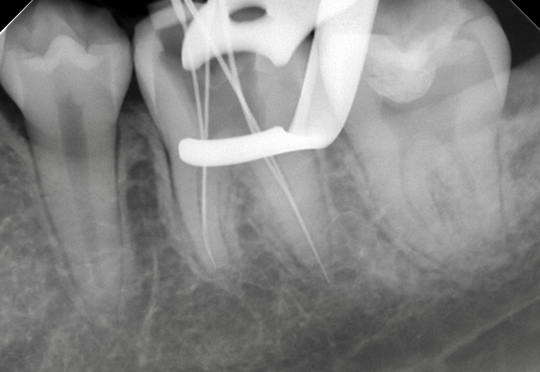

精密根管治療(自費根管治療)治療開始

精密根管治療(自費根管治療)、治療回数4回、治療期間約1ヶ月、治療費(大臼歯再治療)15万3千円+4,500円X4回X2本 ジルコニアクラウン6万9千円X2本

レントゲン写真

ラバーダムシートを固定する金具が写っています、シートはバイ菌が

入らないように撮影時にも外しません

充填物がきちっとできるように何度も確認します

見た目よりもいかに無菌的に行えたかが大切です、見た目もきちっとできました